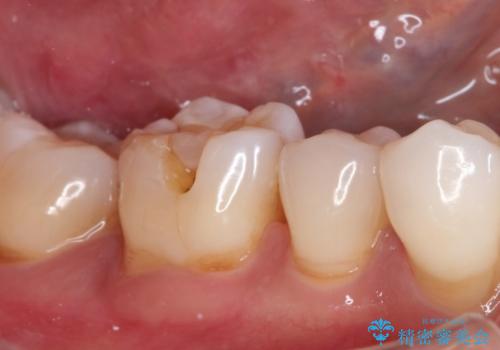

- 以前治療した歯が欠けたことを主訴に来院されました。

見た目もよく強度の高いものでの修復を希望されましたのでセラミックインレーにて修復しました。

当院でのセラミックインレーは歯とのつなぎ目を拡大鏡で確認して精度高く仕上げるため、むし歯のリスクを限りなく少なくできるよう治療します。